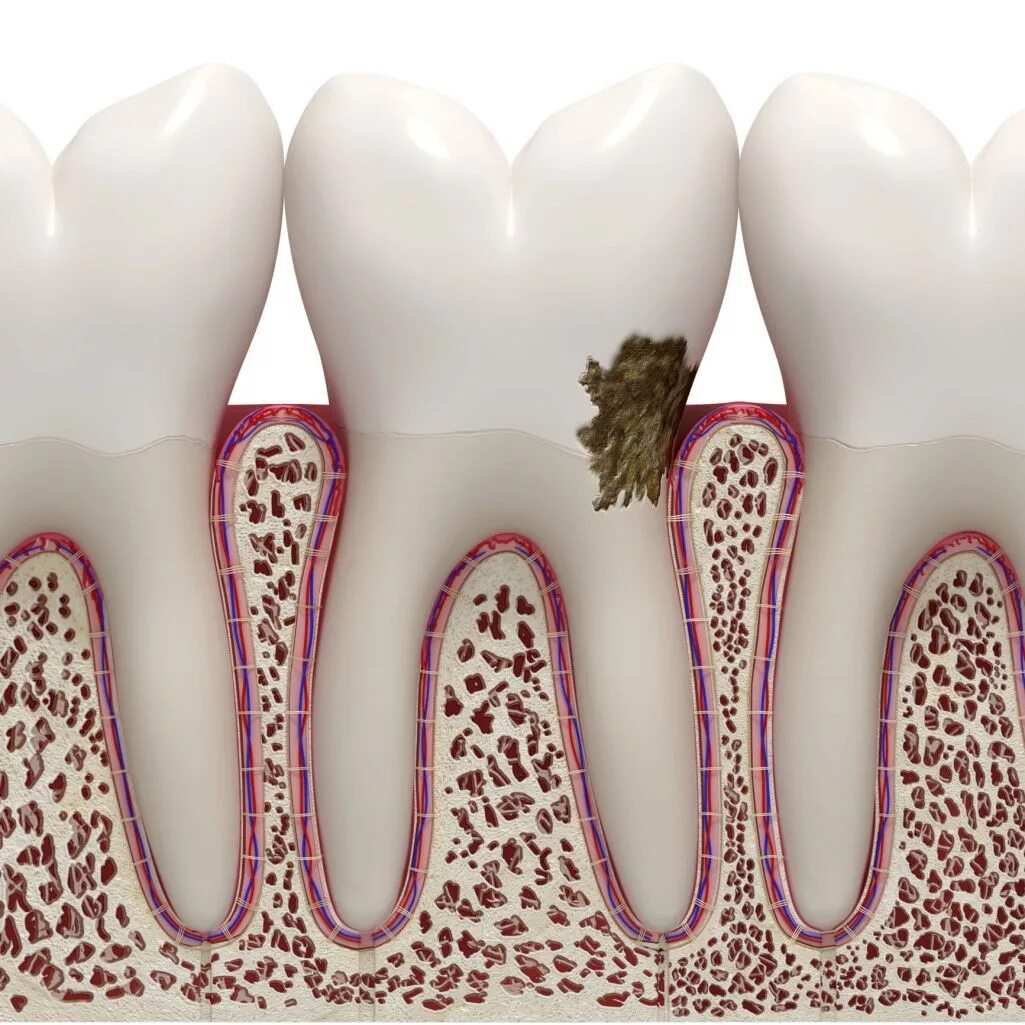

Сообщающаяся с полостью зуба